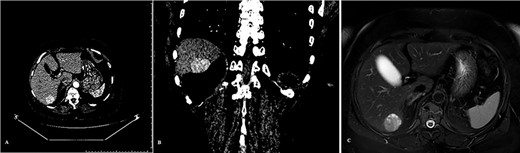

A transabdominal and endoscopic ultrasound also did not reveal any pathological findings in the pancreas. Contrast-enhanced CT and MRI scans of the abdominal cavity were then performed. A tumor of the pancreas was not revealed, although a pathologic mass in the sixth segment of the liver was detected (Fig. 1).

Tumor of the liver detected on the pre-operative diagnostics: (A) CT scan arterial phase frontal projection, (B) CT scan arterial phase frontal projection and (C) MRI scan, axial projection.